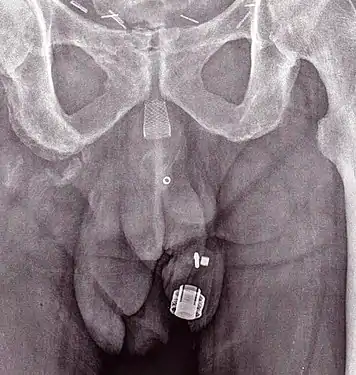

تصوير بأشعة اكس يظهر مصرة ZSI 375 عند رجل. الجهاز غير مفعل، حيث يمكن رؤية النابض تحت مستوى الأسطوانة.